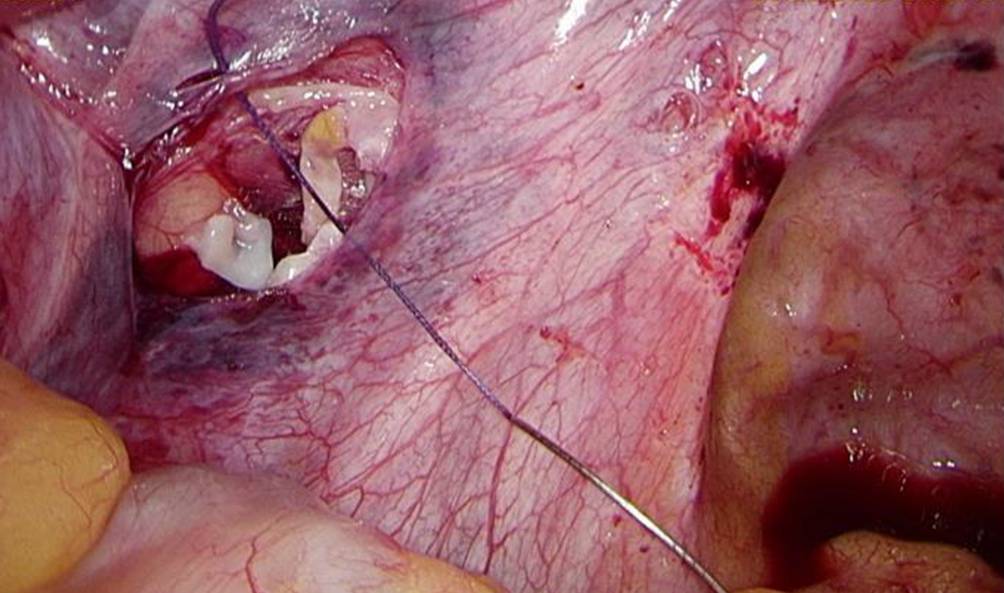

Im Alter von 27 Jahren wurde sie, bei nun vorhandenem Kinderwunsch, an eine Kinderwunschklinik überwiesen. Hier wurde das zuvor kryokonservierte Ovarialgewebe laparoskopisch retransplantiert. Dabei wurde das Ovarialgewebe in das noch vorhandene rechte Ovar und in eine neu angelegte peritoneale Tasche in der Fossa ovarica links retransplantiert (s. Abb. 1).

Abb. 1

Die neu angelegte peritoneale Tasche mit Fragmenten des retransplantierten Ovarialgewebes